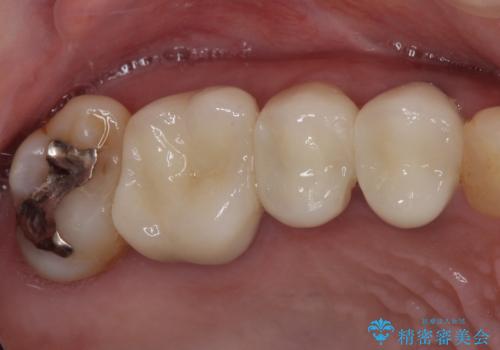

気になる部分を全て治療 総合歯科治療で口腔内環境改善

- 右下の欠損部の治療を希望して来院された患者様です。

部分矯正を行った後にインプラント埋入と手前の歯の根管治療を行い、その後補綴治療を行うこととしました。

治療途中より、上の歯や反対側の銀歯、上顎前歯の色合いや下顎前歯のデコボコが気になってきたため、全てを治療することとしました。

仕事が多忙な方で、来院間隔が開いてしまうことが多く、治療期間はかかりましたが、来院回数は最小限で終えることができました。